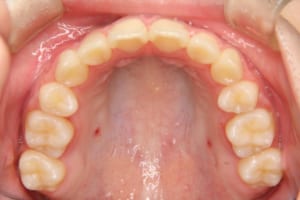

治療後

| その他/備考 | 上の犬歯が生えるためのスペースが全くない状態でした。放置すると重度の八重歯になることが想定されるケースです。 今回はあごの成長も利用しながら治療をするために、早めに後期治療(大人の矯正治療)に移行しました。 治療後レントゲン写真を見たところ、上顎前歯に若干の歯根吸収を認めました。 |